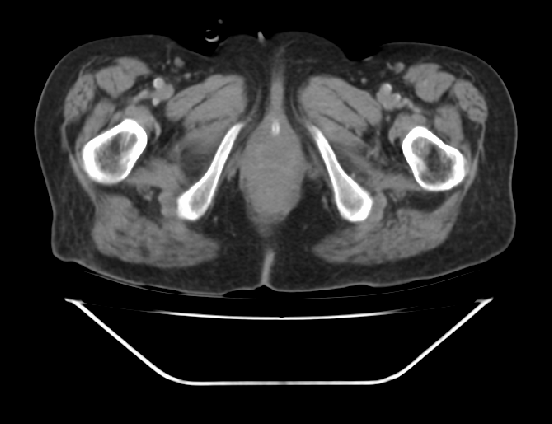

ist jemand unter Euch der sich auskennt mit CT Aufnahmen ?

Ich habe 3 Stück angehangen, sie stammen aus einem CT der Abdomen.

Möglich das es eine Serie eines Querschnitts darstellt Bild 1 zeigt den Start,Bild 2 eines aus den mittleren Aufnahmnen und Bild 3 das letzte dieser CT Serie.

Da ganz gezielt auf ein und die gleiche Stelle gehalten wurde mit sagenhaften über 80 Einzelaufnahmen interessiert mich brennend um die Darstellung welches Organges es sich bei diesen Aufnahmen handelt und ob darauf etwas bedenkliches eingekreist wurde.